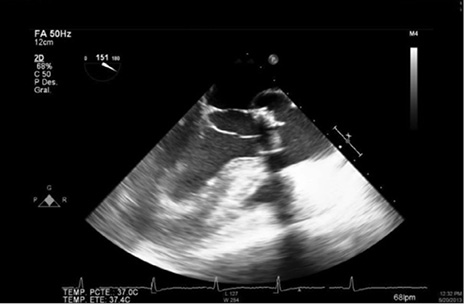

Un mes después del alta hospitalaria, es decir, dos meses luego de la cirugía valvular es valorado por cirugía cardiovascular en consulta externa, observándose en regulares condiciones generales, taquicárdico, polipneico. Se hospitaliza, se inician estudios, documentando nuevamente bacteriemia por P. aeruginosa resistente, razón por la cual se sospecha posibilidad de EI. Se realiza ecocardiograma transesofágico, hallando vegetación adherida a la prótesis biológica de la válvula aórtica, 9 mm (ver Figuras 1-2). Por alteraciones comportamentales concomitantes se ordena una tomografía computarizada (TC) cerebral, observando una zona de hipodensidad que compromete el lóbulo parietal izquierdo y en la topografía de la corteza pre-motora derecha, borramiento de surcos cerebrales, hallazgos compatibles con infartos subagudos probablemente de origen embólico (ver Figura 3) y, por descenso progresivo de hemoglobina sin foco claro, asociado a ascitis, se realiza TC contrastado de abdomen, documentando una zona de infarto segmentario a nivel del polo superior del bazo (ver Figura 4), interpretado como embolismo séptico.

Figura 1: Vegetación adherida a la prótesis biológica de la válvula aórtica.

Figura 2: Vegetación adherida a la prótesis biológica de la válvula aórtica.